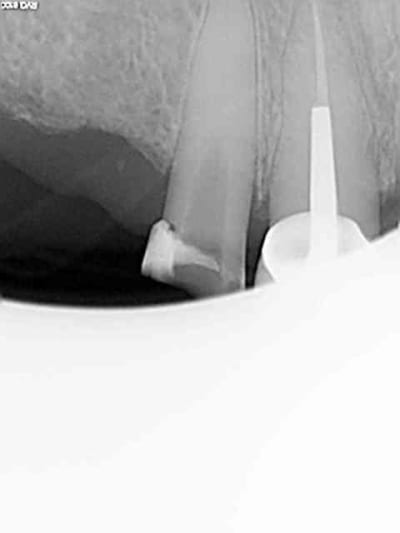

Exemple sur cette 12 tout à l'heure, 1h 30 de rdv terminé en 1h et encore j'ai un peu "tâtonné" pour trouver la pulpe. Toujours pas de cathétérisme manuel of course sinon j'y serais encore.)))))